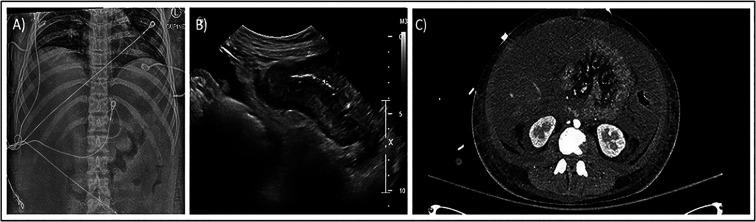

Clostridioides (formerly Clostridium) difficile is the most important infectious cause of antibiotic-associated diarrhea worldwide and a leading cause of healthcare-associated infection in the United States. The incidence of C. difficile infection (CDI) in children has increased, with 20 000 cases now reported annually, also posing indirect educational and economic consequences. In contrast to infection in adults, CDI in children is more commonly community-associated, accounting for three-quarters of all cases. A wide spectrum of disease severity ranging from asymptomatic carriage to severe diarrhea can occur, varying by age. Fulminant disease, although rare in children, is associated with high morbidity and even fatality. Diagnosis of CDI can be challenging as currently available tests detect either the presence of organism or disease-causing toxin but cannot distinguish colonization from infection. Since colonization can be high in specific pediatric groups, such as infants and young children, biomarkers to aid in accurate diagnosis are urgently needed. Similar to disease in adults, recurrence of CDI in children is common, affecting 20% to 30% of incident cases. Metronidazole has long been considered the mainstay therapy for CDI in children. However, new evidence supports the safety and efficacy of oral vancomycin and fidaxomicin as additional treatment options, whereas fecal microbiota transplantation is gaining popularity for recurrent infection. Recent advancements in our understanding of emerging epidemiologic trends and management of CDI unique to children are highlighted in this review. Despite encouraging therapeutic advancements, there remains a pressing need to optimize CDI therapy in children, particularly as it pertains to severe and recurrent disease.